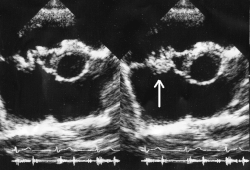

- ECHO serca

- obecność wegetacji – badanie nie pozwala odróżnić zmian powstałych podczas wcześniejszych epizodów choroby od świeżo powstałych

- cechy uszkodzenia aparatu zastawkowego: niedomykalność, tętniak zastawki mitralnej, tętniak rzekomy, ropnie, przetoki wewnątrzsercowe

- protezy zastawkowe uniemożliwiają wykrycie wegetacji, niemożliwe bywa też odróżnienie zwyrodnienia elementów zastawki naturalnej od małych wegetacji

- Wykazanie w badaniu ECHO narośli bakteryjnych, ropni wewnątrzsercowych, nowego przecieku okołozastawkowego lub nowej niedomykalności zastawkowej.

- Wynik badania ECHO sugerujący zapalenie wsierdzia, lecz nie spełniający dużych kryteriów.

- badanie echokardiograficzne – przezklatkowe (TTE) lub przezprzełykowe (TEE; u chorych z ujemnym wynikiem TTE i dużym prawdopodobieństwem choroby, u chorych ze sztuczną zastawką, u chorych z zajęciem zastawki aortalnej oraz przed operacją); niekiedy celowe jest uzupełnienie badania echokardiografią kontrastową;

- badanie echokardiograficzne – do oceny uszkodzenia zastawek i tkanek okołozastawkowych, także po zakończeniu leczenia;